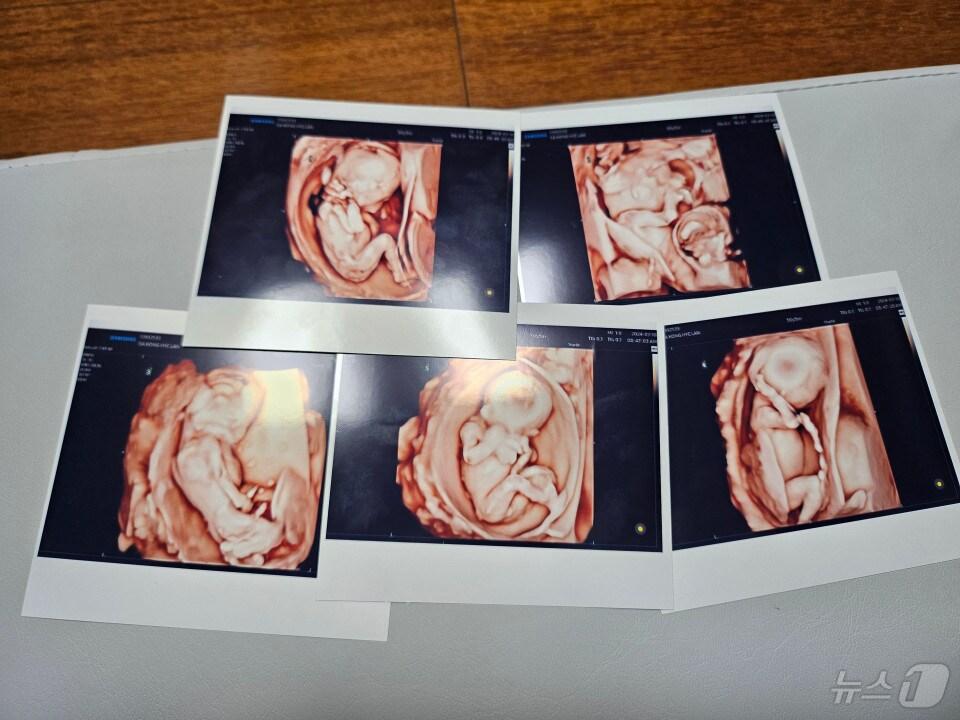

이주호, '다섯쌍둥이' 출산한 교육공무원 부부에 축하 전달서울성모병원 제공관련 키워드교육부이주호장성희 기자 "브레이크 작동 안 해"…서대문역 시내버스 돌진, 13명 부상(종합2보)서대문역 인근 시내버스 돌진…중상 2명 등 13명 부상(종합)관련 기사윤곽 드러나는 서울교육감 후보…정근식·강민정·조전혁·임해규尹 정부, 연 구독료 1조 AI교과서…시범운영 없이 추진, 활용률 8.1%의협 "尹 정부 의대 증원 추진 위법" 尹 고발…직권남용 등 혐의김현철·한만중 출사표…조희연 참모 출신들 서울교육감 도전김현철 전 서울교육청 대변인, 교육감 출마…진보교육계 첫 선언